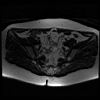

bekken